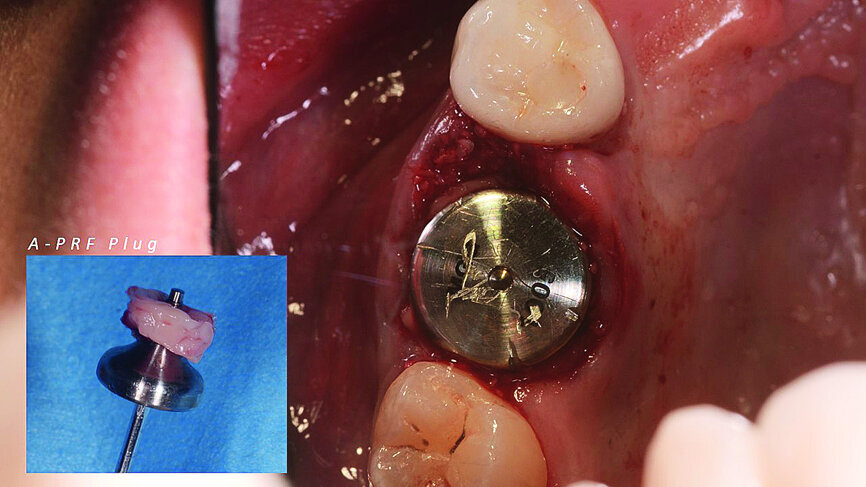

Once the implant bed had been prepared, a 7 × 10 mm implant (AnyRidge) was placed. After placement, the ISQ (Implant Stability Quotient) was measured with a stability meter (Mega ISQ, MegaGen), and the value was 72. According to the ISQ scale, this represents high stability (Fig. 6b). A 10 × 7 mm healing screw (AnyRidge) was placed, along with a plug of A-PRF (advanced platelet-rich fibrin; PRF process by Choukroun) in order to accelerate the healing process, and sutured with 4/0 polypropylene (Hu-Friedy; Figs. 7–10). After the surgical procedure, the White Clinic postoperative protocol was applied: application for eight minutes of the ATP38 laser (Swiss Bio Inov), based on the principle of Low Level Laser Therapy that acts on the cellular metabolism and provides a better and faster postoperative healing. The patient was instructed to use a 0.2% hyaluronic acid gel (Gengigel, Ricerfarma) and 0.1% hyaluronic acid mouthwash (Gengigel First-aid, Ricerfarma) for one week after surgery, with the goal of accelerating the healing process. One week after surgery, the sutures were removed, ozone was used to disinfect the area around the implant, and the ATP38 was applied for eight minutes to promote healing.